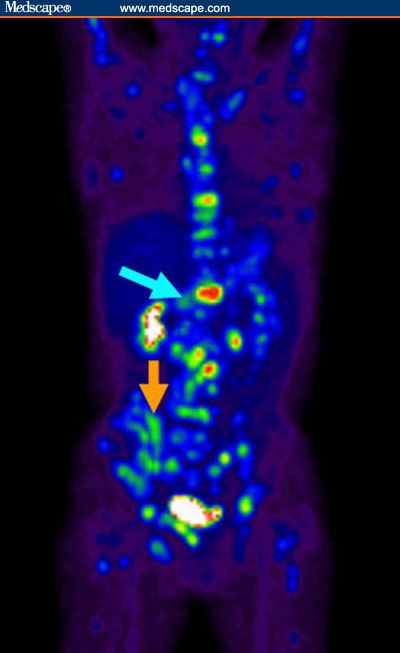

림프종 환자의 PET-CT 사진. 본 사진은 글의 내용과 무관합니다. 출처: www.medscape.com

PET-CT에는 종양이 검은 색 배경에 밝은 불빛으로 나타난다. 온 몸의 여기저기에 다 퍼진 전이암이 한꺼번에 불빛을 발하듯이 나타난 그 사진에는 아마 몸이 크리스마스 트리처럼 보였을 것이다. 더 빛날 수록 더 절망스러운 그런 사진. 나는 오늘 아침에도 보았다. 쓸 수 있는 항암제를 다 쓰고 마지막 희망을 안고 임상시험치료를 하러 입원한 한 남자의, 크리스마스 트리같던 몸을. 항암치료를 쉬어도 기운이 점점 없어지고 입맛이 더 떨어지더라는, 그의 낙심한 눈빛을. 그의 몸에서 타고 있는 불꽃들을 이 약이 조금이라도 꺼뜨려줄 수 있다면 좋을텐데.

의사가 PET 검사를 권하는 환자들은 대개 전이암이 있는 환자들이다. CT 만으로는 감별이 안되는 병변을 확인하거나, 또는 항암제 치료 전후의 암세포의 대사 정도를 비교하기 위해 찍는다. FDG-PET은 포도당을 많이 섭취하는 암세포의 성질을 이용하는 검사다. 만약 항암제가 효과를 보이면서 암세포가 죽거나 성장이 정체되면 포도당 섭취가 감소하면서 사진에서 보이는 빛이 줄어든다.

환자에게 PET 사진을 보여주며 설명을 하는 경우는 크게 두 가지다. 하나는 (대개는 잠시나마) 치료 후 저 빛이 꺼진 것을 확인하여 기쁨을 주기 위해. 또 하나는.... 전이암이라고 설명을 드렸음에도 수술할 수 있지 않느냐고 반복해서 물어보는 환자와 가족에게 확인을 시켜주기 위해 보여준다. 당신의 몸은 크리스마스 트리처럼 빛나고 있어서, 불붙은 가지 하나를 꺾는 것으로 해결되지 않는다고. 우선은 소화기를 써야 한다고. 하얀 가루를 뒤집어쓰는게 싫더라도 지금은 그걸 써야 한다고. 그렇게 하더라도 다 꺼질 지 모르는, 불씨가 하나라도 남아있으면 다시 번지고 마는 그런 불이라고. 그런 말을 들으면 환자는 아마 새까맣게 타들어가는 심정이 될 것이다. 그렇더라도 누군가는 해야 할 말. PET-CT에 나타난 크리스마스 트리는 절망에 쐐기를 박는 너무나 강렬한 이미지여서, 자신의 상태를 부정하는 환자에게 병에 대한 인식을 줄 때 유용하기는 하다. 그러나 기술의 발전이 주는 혜택 치고는 참으로 공허하다. 물론 PET은 이러려고 만든 기술은 아니고 주로 진단의 정확도를 올리고 치료 반응을 예측하는 것이 주된 목적이지만.